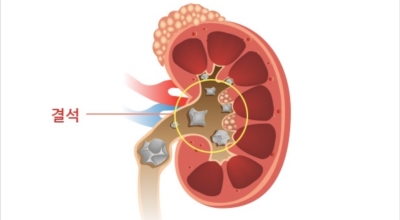

요로결석의 치료방법은 당연히 결석을 제거하는 방법이 최우선인데요 체외충격파 쇄석술 이라고 하는 시술을 통해 결석을 자연 배출될 수 있도록 하는 방법이 있습니다. 충격파 장치에서 고에너지 충격파를 쬐어 결석을 파괴하면, 결석 조각이 알아서 배출될 수 있도록 하는 시술입니다.

입원이 필요치 않은 시술이며 시술 후 1시간이면 바로 일상 회복이 가능하다고 해요. 물론 더 심한 경우는 내시경 결석 제거술등의 수술을 통해 제거해야 하는 경우도 있어요. 그렇기 때문에 증상이 발생한 초기에 빠르게 대응하여 간단한 시술로 결석을 없애는 것이 최우선입니다.